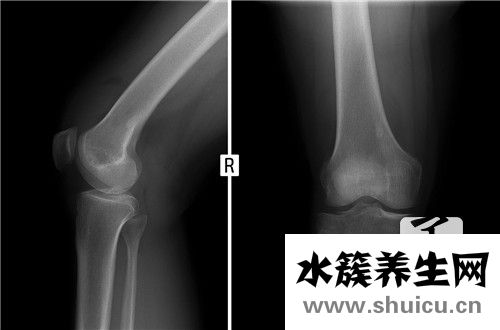

橈骨小頭骨折是普遍的手肘損害,占全身骨折的0.8%,約有l(wèi)/3病人合拼骨節(jié)別的位置損害。橈骨小頭骨折是骨節(jié)內(nèi)骨折,如果有挪動(dòng),理當(dāng)割開復(fù)位內(nèi)固定不動(dòng),修復(fù)解剖學(xué)部位,初期活動(dòng),以修復(fù)腕關(guān)節(jié)伸曲和上臂轉(zhuǎn)動(dòng)作用。

該病由立即外力作用造成的骨折非常少見。普遍的是腕關(guān)節(jié)挺直位跌倒,手掌心碰地,外力作用使橈骨頭出外翻位與肱骨小頭碰撞而造成骨折。常合拼肱骨小頭損害與內(nèi)側(cè)副韌帶損害。常見于成人且非常容易誤診。若不可以獲得早期治療,一些病人上臂轉(zhuǎn)動(dòng)作用受限制,迫不得已將橈骨小頭摘除。

傷后肘兩側(cè)局限發(fā)脹、疼痛,橈骨頭周邊有顯著的壓疼。上臂轉(zhuǎn)動(dòng)活動(dòng)受到限制,處于被動(dòng)活動(dòng)時(shí)疼痛,尤其是在旋后時(shí)顯著。腕關(guān)節(jié)功能問題,伸屈疼痛加劇。依據(jù)Mason分析法可分成三種種類:

I型:橈骨小頭骨折但無挪動(dòng)。骨折線能夠根據(jù)橈骨小頭邊沿或破裂狀,有時(shí)候斜行根據(jù)關(guān)節(jié)面。

Ⅱ型:橈骨小頭骨折并有分離出來挪動(dòng)。骨折塊有尺寸,有時(shí)候小骨折片置入骨節(jié)空隙或礦酸于肱橈關(guān)節(jié)兩側(cè)緣。

Ⅲ型:橈骨小頭粉碎性骨折。橈骨小頭呈破碎狀,挪動(dòng)或無挪動(dòng)。有時(shí)候骨折片呈崩裂狀向周邊分離出來挪動(dòng),也是有呈坍塌骨折。

這類三型分析法可以意味著損害水平,并可出示挑選治療方法的根據(jù)。